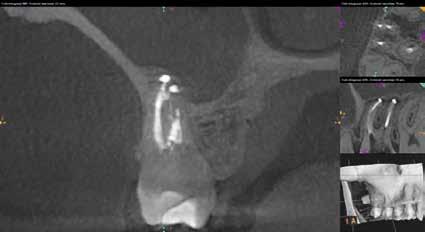

1. ábra: Kiindulási röntgenfelvétel. – 2. a–c. ábra: A horizontális irányú metszeten kiterjedt csontpusztulás jelei láthatóak (a), a vertikális irányú metszeteken mindkét középső metszőfognak megfelelően észlelhető a csontpusztulás (b–c).

3. ábra: Az eset ellátása során a „rezekciómentes” technikát alkalmaztuk. – 4. a–b ábra: Posztoperatív kontrollröntgen (a), 9 hónappal később készített kontrollfelvétel (b).

Egy fiatal hölgy, aki modellként dolgozik és emiatt nagy jelentőséget tulajdonít a saját fogai megőrzésének, a két középső alsó metszőfoga alatt kialakult duzzanat miatt kereste fel a rendelőnket. Vizsgálatot követően megállapítottuk, hogy a fogak mellett 20 mm szélességű tasak van jelen, amely az egyik alsó középső metszőfog disztális oldalától a másik alsó középső metszőfog disztális felszínéig terjed. Ebből az következik, hogy ezen a területen a teljes bukkális kortikális csontlemez leépült. Mindkét fog III. fokú mobilitással rendelkezett, amely tovább rontotta a kérdéses fogak várható prognózisát. Szenzibilitásvizsgálatot is végeztünk. A két alsó középső metszőfog esetében a páciens nem jelzett hidegingert, de a többi fog esetében fiziológiás választ adott. Periapikális röntgenfelvétel készült, amelyen nem mutatkozott meg a vélelmezett elváltozás (1. ábra). Ennek megfelelően CBCT-felvételt készítettünk, hogy jobban meg tudjuk vizsgálni a kérdéses területet. Ezen a felvételen már láthatóvá vált a vertikális és horizontális irányú csontpusztulás tényleges mértéke. A horizontális síkban készített metszeten a két alsó középső metszőfog körül megfigyelhető volt a bukkális kortikális csontlemez és a szivacsos csontállomány hiánya. A defektus szélessége 14,11 mm, a mélysége pedig 6,28 mm volt (2. a. ábra). A vertikális irányú metszeten láthatóvá vált, hogy a középső metszőfogak gyökerének bukkális oldalát nem fedi csont, és ez a defektus már a gyökércsúcsok alatti területre is kiterjedt (2. b–c. ábra)